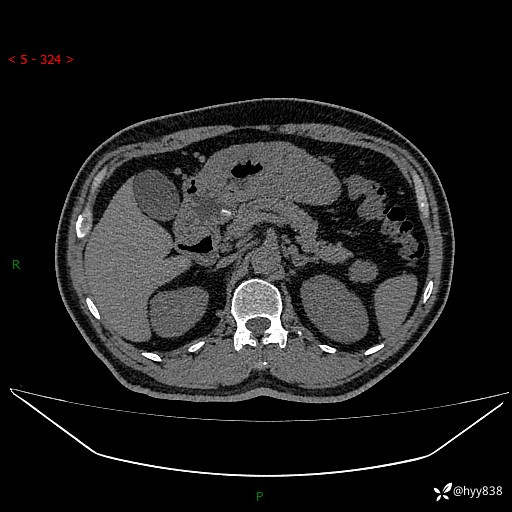

胰腺CT平扫